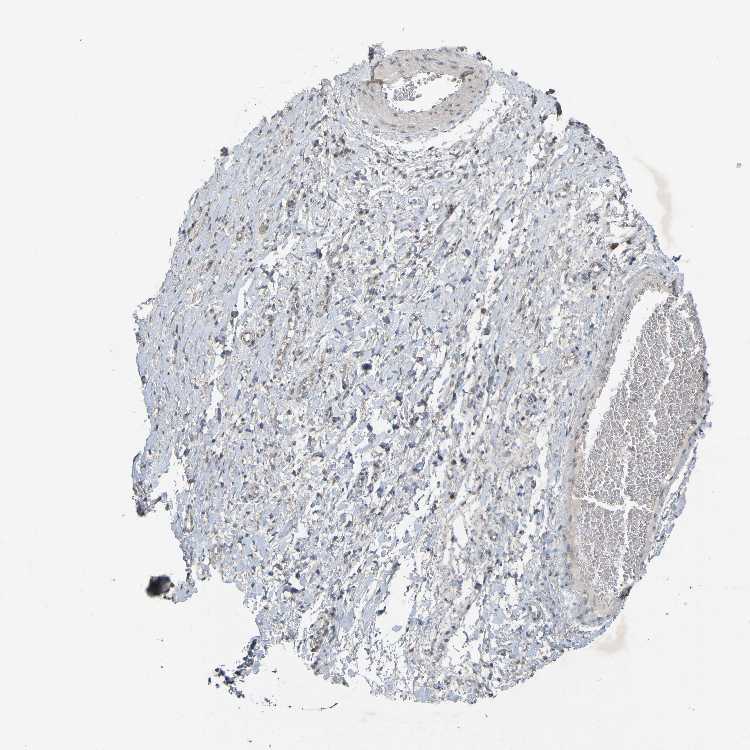

PRKCG